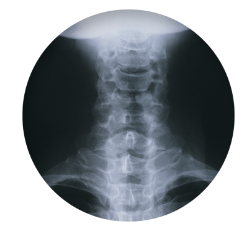

목디스크 증상 원인 치료방법 등 목 디스크 관련 정보에 대해 알아보도록 하겠습니다. 목디스크는 인간의 척추 중 경추부나 흉추부에 위치한 디스크(틀니)가 변형되어 생긴 질환으로, 경추부의 경우 목의 통증, 저림 혹은 근육 경련, 어깨와 팔의 통증, 감각상실 등이 나타나며, 흉추부의 경우 흉부의 통증, 등의 통증 등이 나타납니다. 보통은 원인불명성으로 인한 자연적인 회복을 기다리는 것이 가장 좋으며, 통증이 심한 경우 보조적으로 항통제나 근육 이완제 등을 사용합니다. 만약 압력이 심한 경우 수술이 필요할 수 있습니다.예방법으로는 바른 자세 유지와 체중 조절, 충분한 운동, 목과 등의 근육 강화 등이 있습니다.

목 디스크는 경추부나 흉추부의 디스크(틀니) 변형으로 인해 발생하는 질환으로, 다음과 같은 증상이 나타날 수 있습니다.